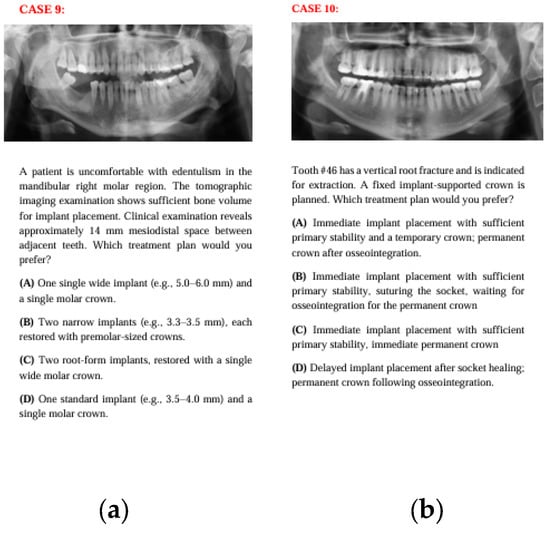

Figure 5. The panoramic radiographs, descriptions, and four treatment options of Case 9 (a) and Case 10 (b).